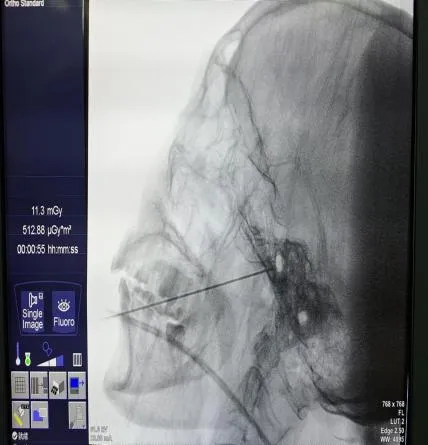

近日一名八十多岁的患者刘奶奶(化名)近3年来饱受左侧额面部发作性疼痛折磨,近期疼痛更是加重,于是前往荣昌区人民医院疼痛科就诊。入院时刘奶奶面容痛苦、精神萎靡,经疼痛评分后为“重度疼痛”,且由于进食、刷牙等诱发疼痛导致无法正常进食与刷牙,刘奶奶还出现全身乏力与多发口腔溃疡等症状。经过术前准备,在DSA引导下行左侧三叉神经半月节微球囊压迫术,术中,医务人员采用专用穿刺针精准穿刺,使用微球囊对三叉神经半月节进行压迫,从而消除了患者的疼痛,整个过程用时不到30分钟,术后,刘奶奶疼痛消失,第2天恢复正常饮食,她的脸上露出了久违的笑容。

近一年来,荣医疼痛科在C型臂或DSA影像引导下运用穿刺针为多名患者实施的三叉神经半月节射频热凝术或三叉神经半月节微球囊压迫术,经术后长期随访,患者疼痛完全消失。